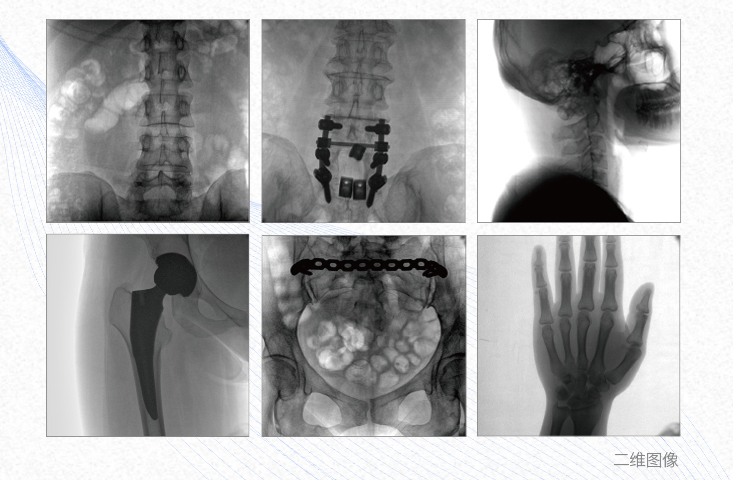

1、脊柱外科

有效重建复杂的脊柱三维模型,提供准确的二维、三维图像,提高螺钉植入的准确性,缩短手术时间,减少并发症的概率,降低辐射的摄入。

2、创伤外科

例如骨盆骨折内固定术,可术中三维重建髋臼关节面,准确定位并植入螺钉,有效缩短螺钉植入的时间和透视暴露时间,减少术中及术后并发症发生的概率。

3、关节外科

主要应用于肩关节、肘关节、髋关节、膝关节的关节置换及解剖复位的定位。它可以准确地置入假体,减少辐射时间,降低辐射剂量。

4、截骨矫形外科

例如治疗先天性脊柱侧后凸畸形,可有效引导术者植入后路螺钉并切除半锥体,达到满意的截骨矫正效果。